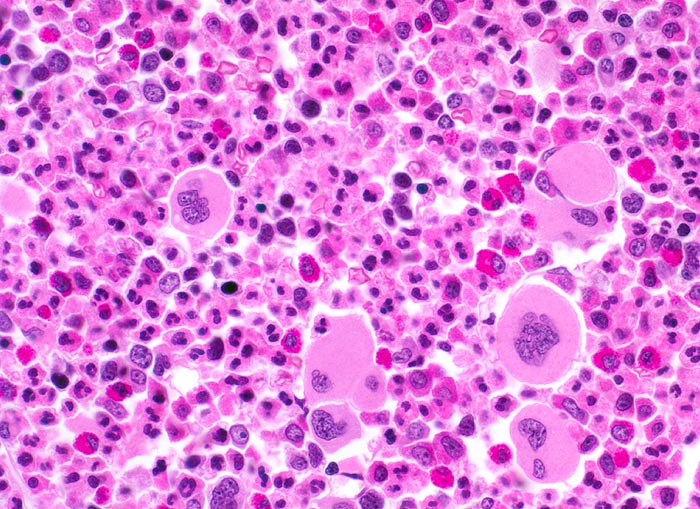

PathoPic – image database / PathoPic ID 3899 - chronische myeloische Leukämie (CML)

chronische myeloische Leukämie (CML)

Knochenmark, Beckenkamm

Ausschnitt aus der Mitte des Markraumes mit Überwiegen reiferer Elemente der Granulozytopoese mit zahlreichen vollständig ausgereiften segmentkernigen neutrophilen Granulozyten und mehreren kräftig roten segmentkernigen eosinophilen Granulozyten. Die verschiedenen unreiferen Zelltypen der Granulopoese können in der HE Färbung nicht sicher voneinander abgegrenzt werden. Nur ganz vereinzelt lassen sich Reste der roten Blutbildung nachweisen. Vermehrte kleine, teils in Gruppen liegende Megakaryozyten mit hypolobierten Kernen.

Müdigkeit und Gewichtsverlust. Ausgeprägte Leukozytose, Basophilie und leichte Anämie. Palpable Milz.

Histologie

Vergrösserung